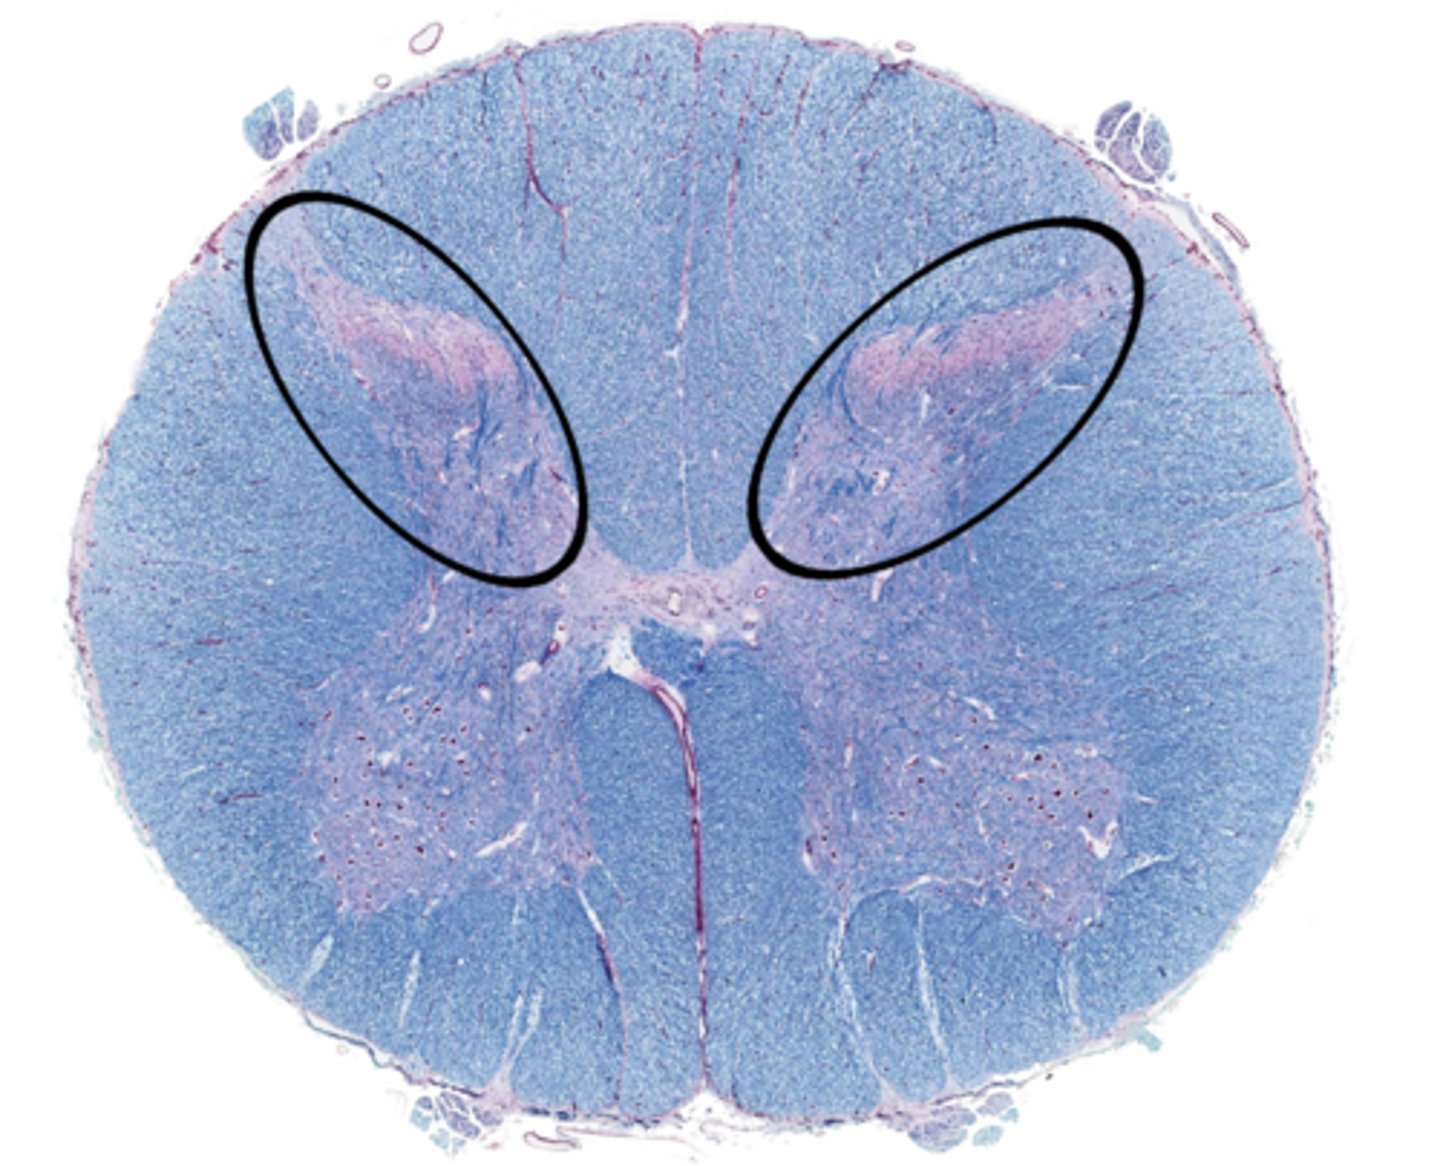

Gray matter

Posterior horn

Anterior horn

Lateral horn

Gray commissure

Central canal

White matter

Posterior funiculus

Anterior funiculus

Lateral funiculus